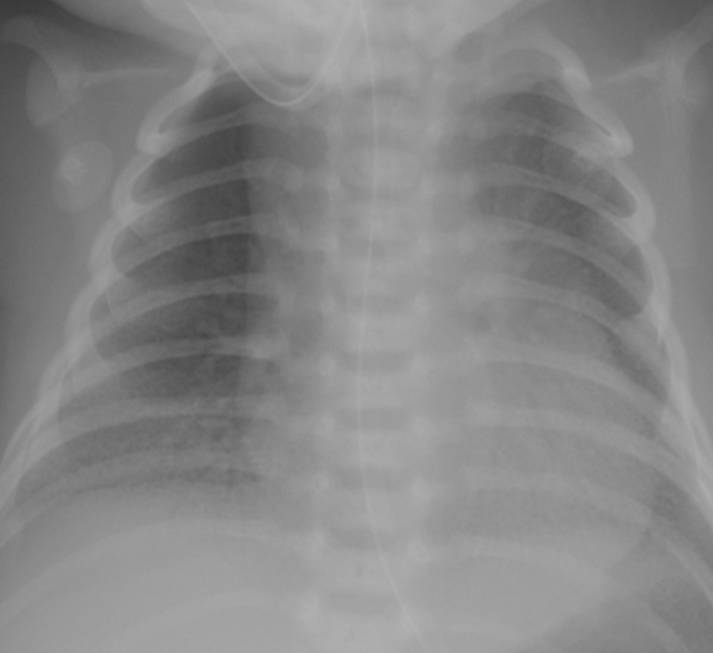

典型胸片結(jié)果:

(II-III級肺透明膜病變)